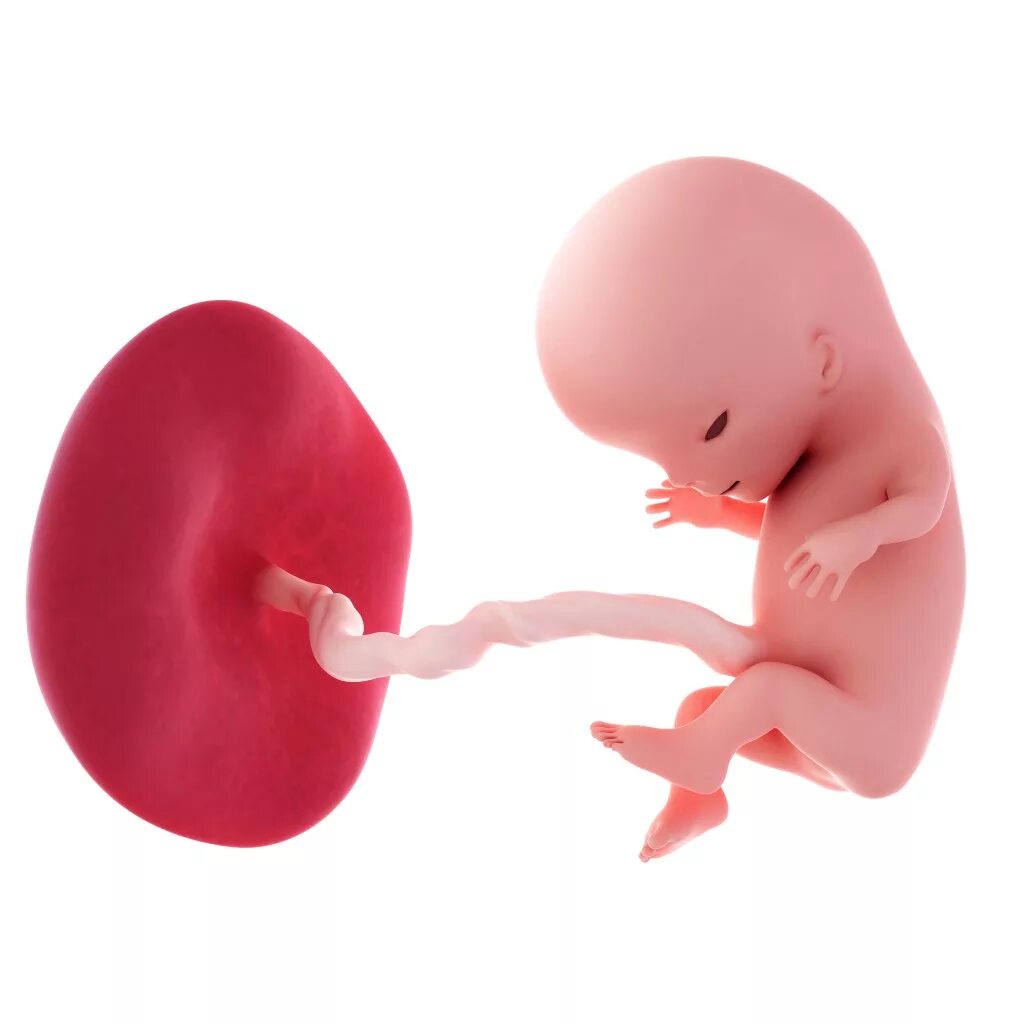

11 недель ощущения